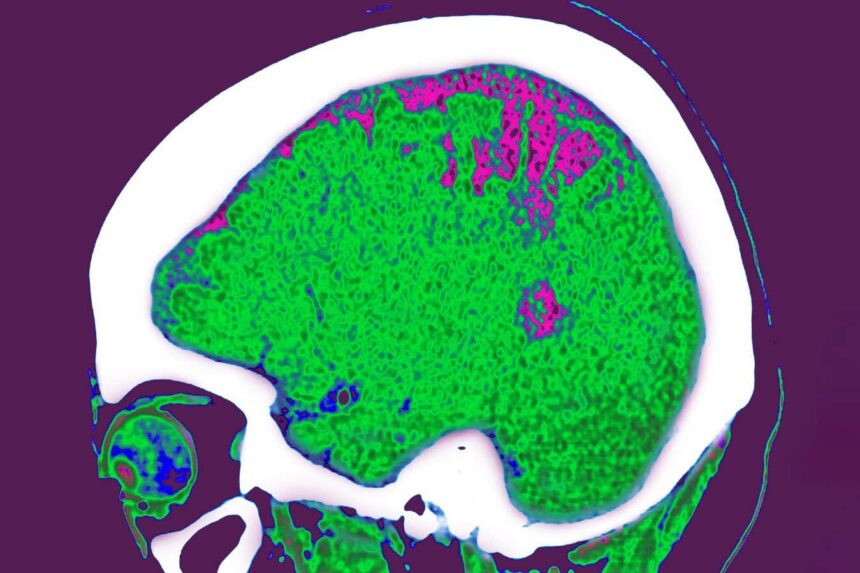

The team collected body composition scans and brain-imaging results from more than 18,000 adults, with an average age of 62, who participated in the UK Biobank project. After accounting for factors such as age, the researchers linked excess fat in each of these regions to distinct brain changes.

For instance, above-average amounts of arm and torso fat were associated with thinning in the sensorimotor cortex, an area involved in movement. Arm fat was also linked with decreased volume in the hippocampus. Crucial for memory, this is one of the first regions affected by Alzheimer’s disease, which may explain why other studies have linked fat storage in the arms with a higher risk of neurodegenerative conditions.

The researchers also found that above-average leg fat was linked to decreased connectivity in the brain’s limbic network, which regulates emotions and reward processing. They think this might be because lower body fat secretes leptin, a hormone that regulates hunger, with higher levels of leptin being associated with reduced limbic connectivity.

But it was having more fat around the internal organs, known as visceral fat, that had the strongest association with altered brain function. This was the only type of fat the team analysed that wasn’t linked with the preservation of white matter, tissue that transmits signals between different brain regions. Instead, it was associated with its deterioration, another hallmark of Alzheimer’s disease.